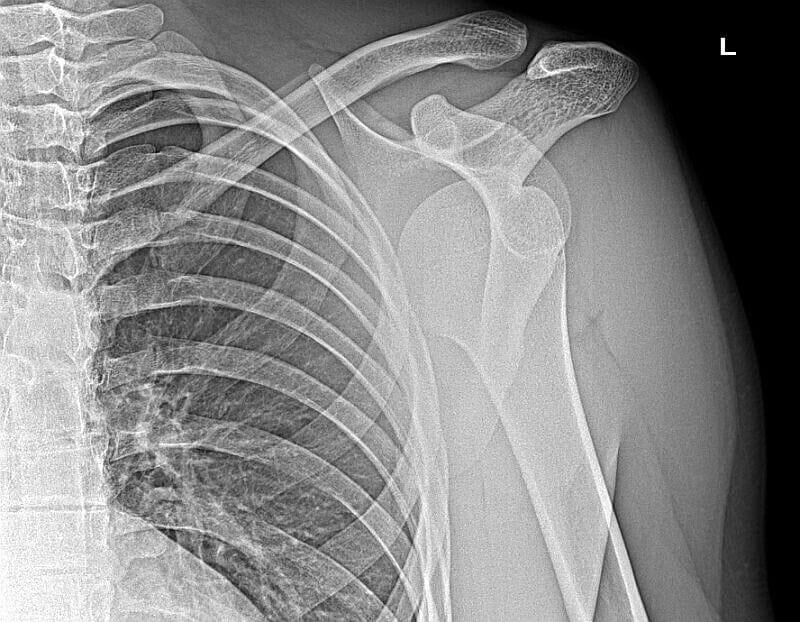

Zwichnięcie barku to jedna z częstszych kontuzji stawu ramiennego. Podobno szczególnie narażeni są na nią sportowcy – na przykład kolarze czy narciarze – i entuzjaści siłowni. Nie oznacza to jednak, że pozostali mogą się czuć niezagrożeni. Może to spotkać każdego. Wystarczy niefortunny upadek na ramię.